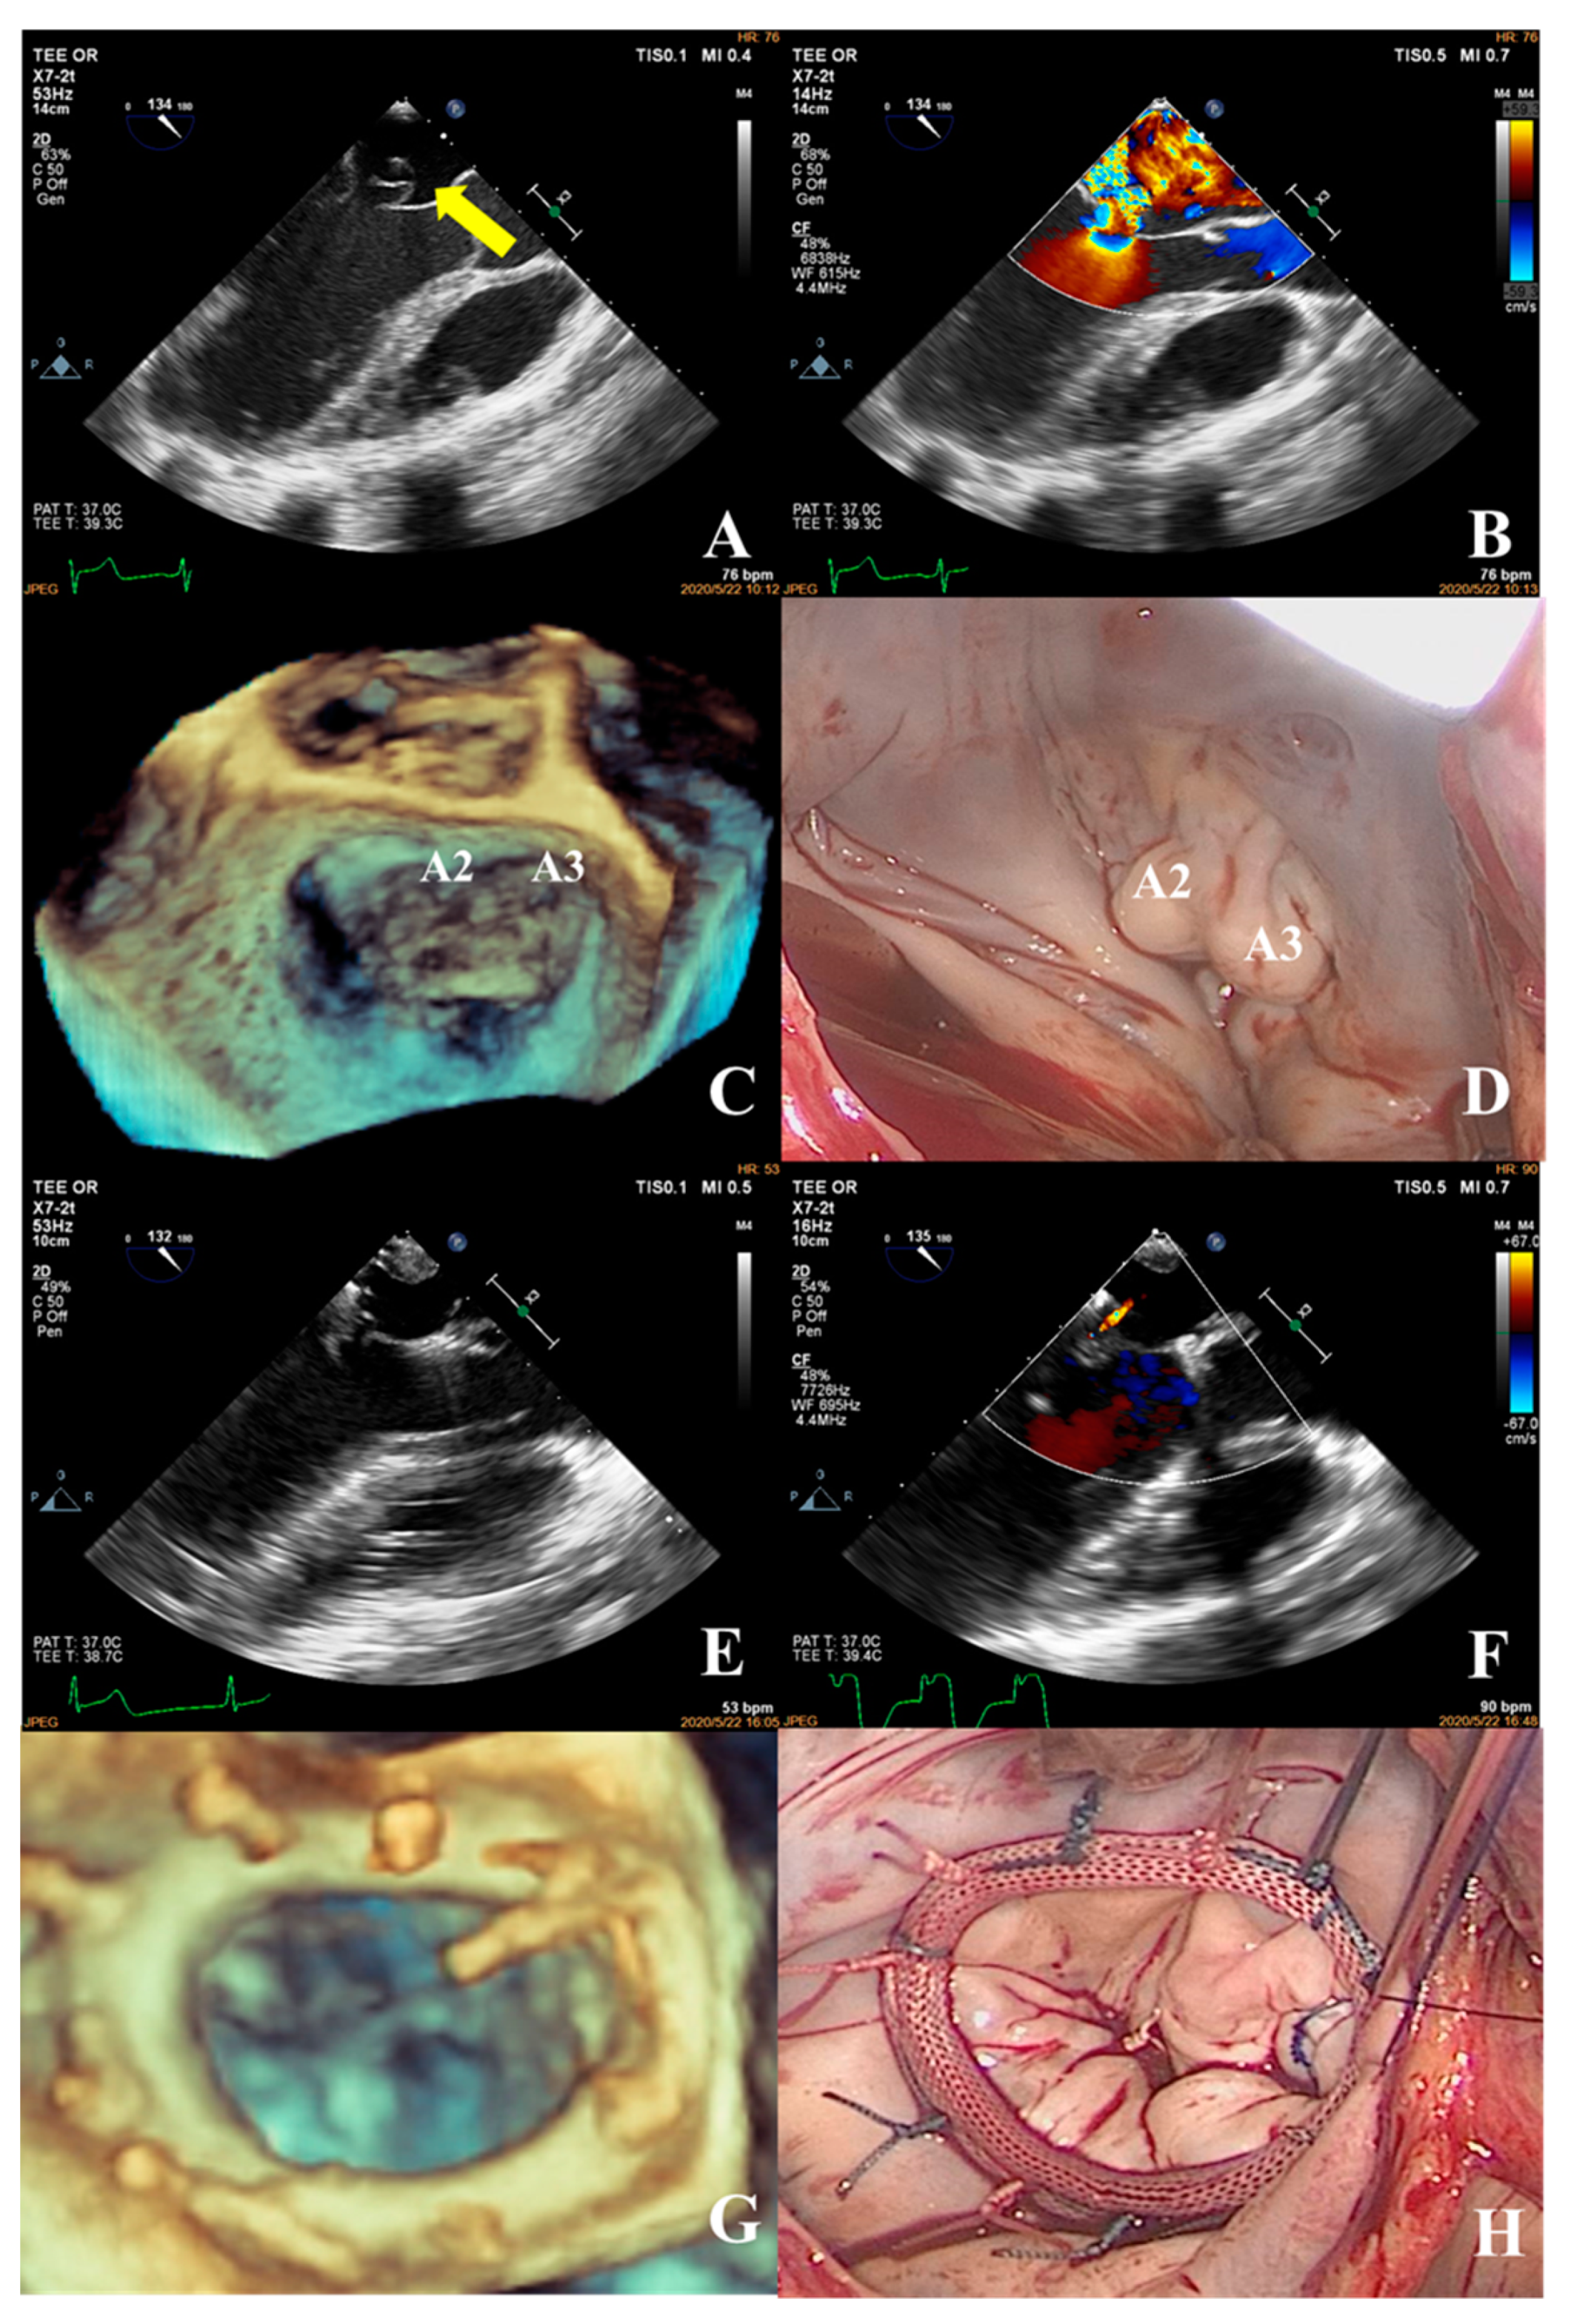

- Patients in the complex group had a variety of etiologies, including multiple segmental mitral valve prolapse (12.5%), Barlow’s syndrome (7.1%), infective endocarditis (12.5%), and rheumatic valvular heart disease (67.9%). The proportion of patients with each of the three less common etiologies was essentially the same. These diseases not only involve a wide range of lesions but are also accompanied by changes in valve morphology and structure, which increases the difficulty of surgery. Preoperative evaluation of the lesion is also a challenge for echocardiologists. A patient with preoperative suspicion of Barlow’s syndrome exhibited prolapse involving the A2 and A3 segments and posteromedial commissure, accompanied by redundant valve leaflets. The complexity score was 9 (2 × 2 + 2 + 3). Two artificial chordae tendineae were implanted in each of the A2 and A3 segments and a mitral annuloplasty ring was placed. The surgical technique score was 5 (4 × 1 + 1) and the surgical effect was good (Figure 9).